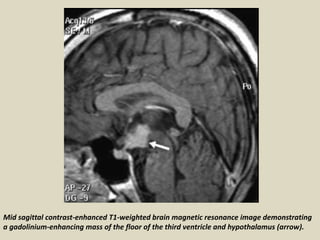

Mid sagittal contrast-enhanced T1-weighted brain magnetic resonance image demonstrating

a gadolinium-enhancing mass of the floor of the third ventricle and hypothalamus (arrow).